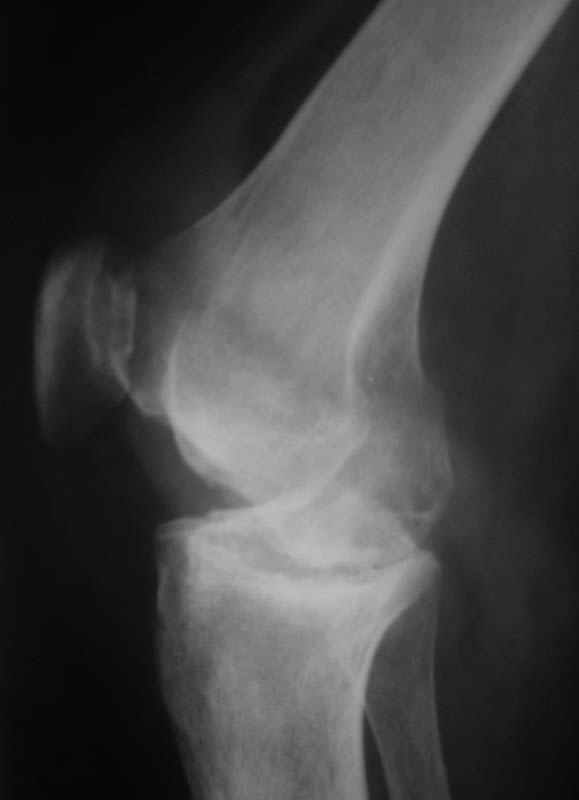

Уважаемые коллеги! Женщина, 28 лет. Страдает ревматоидным полиартритом, гормонозависима. 6 месяцев назад перенесла тотальное эндопротезирование левого тазобедренного сустава по поводу протрузионного коксита.

Использована цементная версия с пластикой дна впадины измельченной аутокостью и гранулами гидроксиапатита. Субъективное улучшение после операции. Улучшилось и стабилизировалось общее состояние. В настоящее время затруднено передвижение из-за поражения правого коленного сустава. Болезненный и <болтающийся> сустав. Предполагается замена сустава протезом без сохранения задней крестообразной связки. Возможные варианты? Заранее благодарю! С уважением,А.В.ВладзимирскийДонецкий НИИ травматологии и ортопедииДонецк, Украина